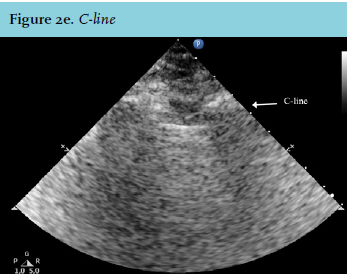

What are “C lines”?

C lines = consolidations = these are not actually artifacts but are soft tissue like regions in direct contact with the visceral pleura

-air bronchograms can usually be seen within these consolidations